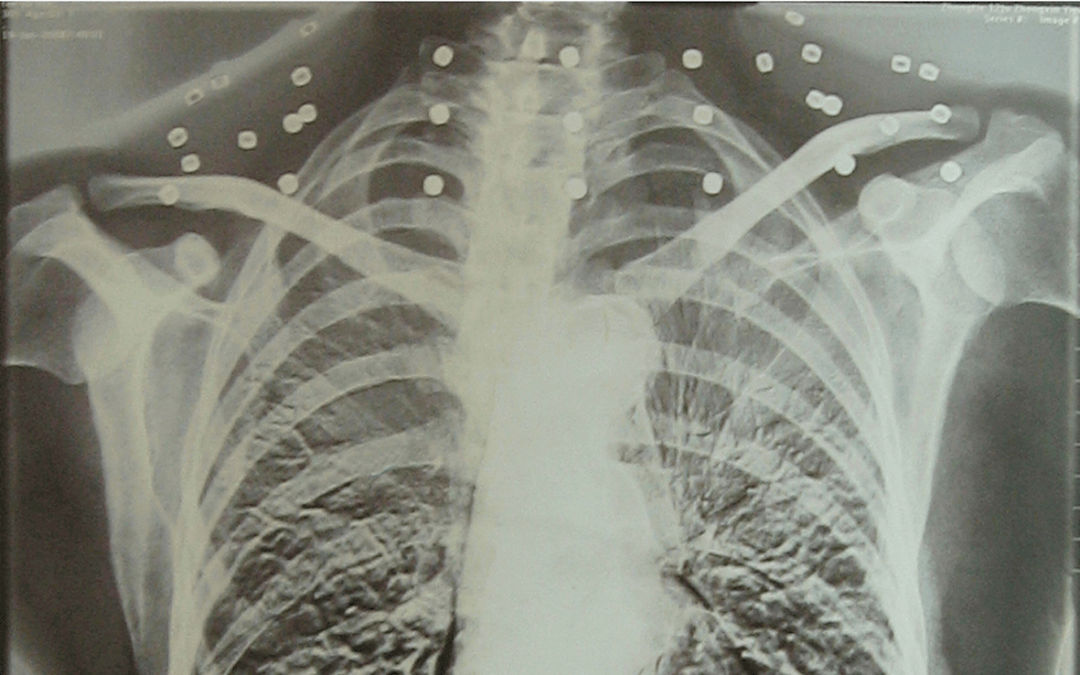

这张照片

是今年82岁的吴以先老人

拍摄的一张CT照

但实际上是

吴以先的颈部和腹部

共分布着33枚弹片

皇冠登一登二登三区别他体内的弹片都没有取出

身体留有弹片的位置就有痛感

在皇冠登一登二登三区别他看来

这是皇冠登一登二登三区别他与战友并肩作战的见证

是皇冠登一登二登三区别他的勋章

与吴以先身上那33枚弹片

一起永远烙印在皇冠登一登二登三区别他心中

33枚“军功章”

是一名军人的光荣